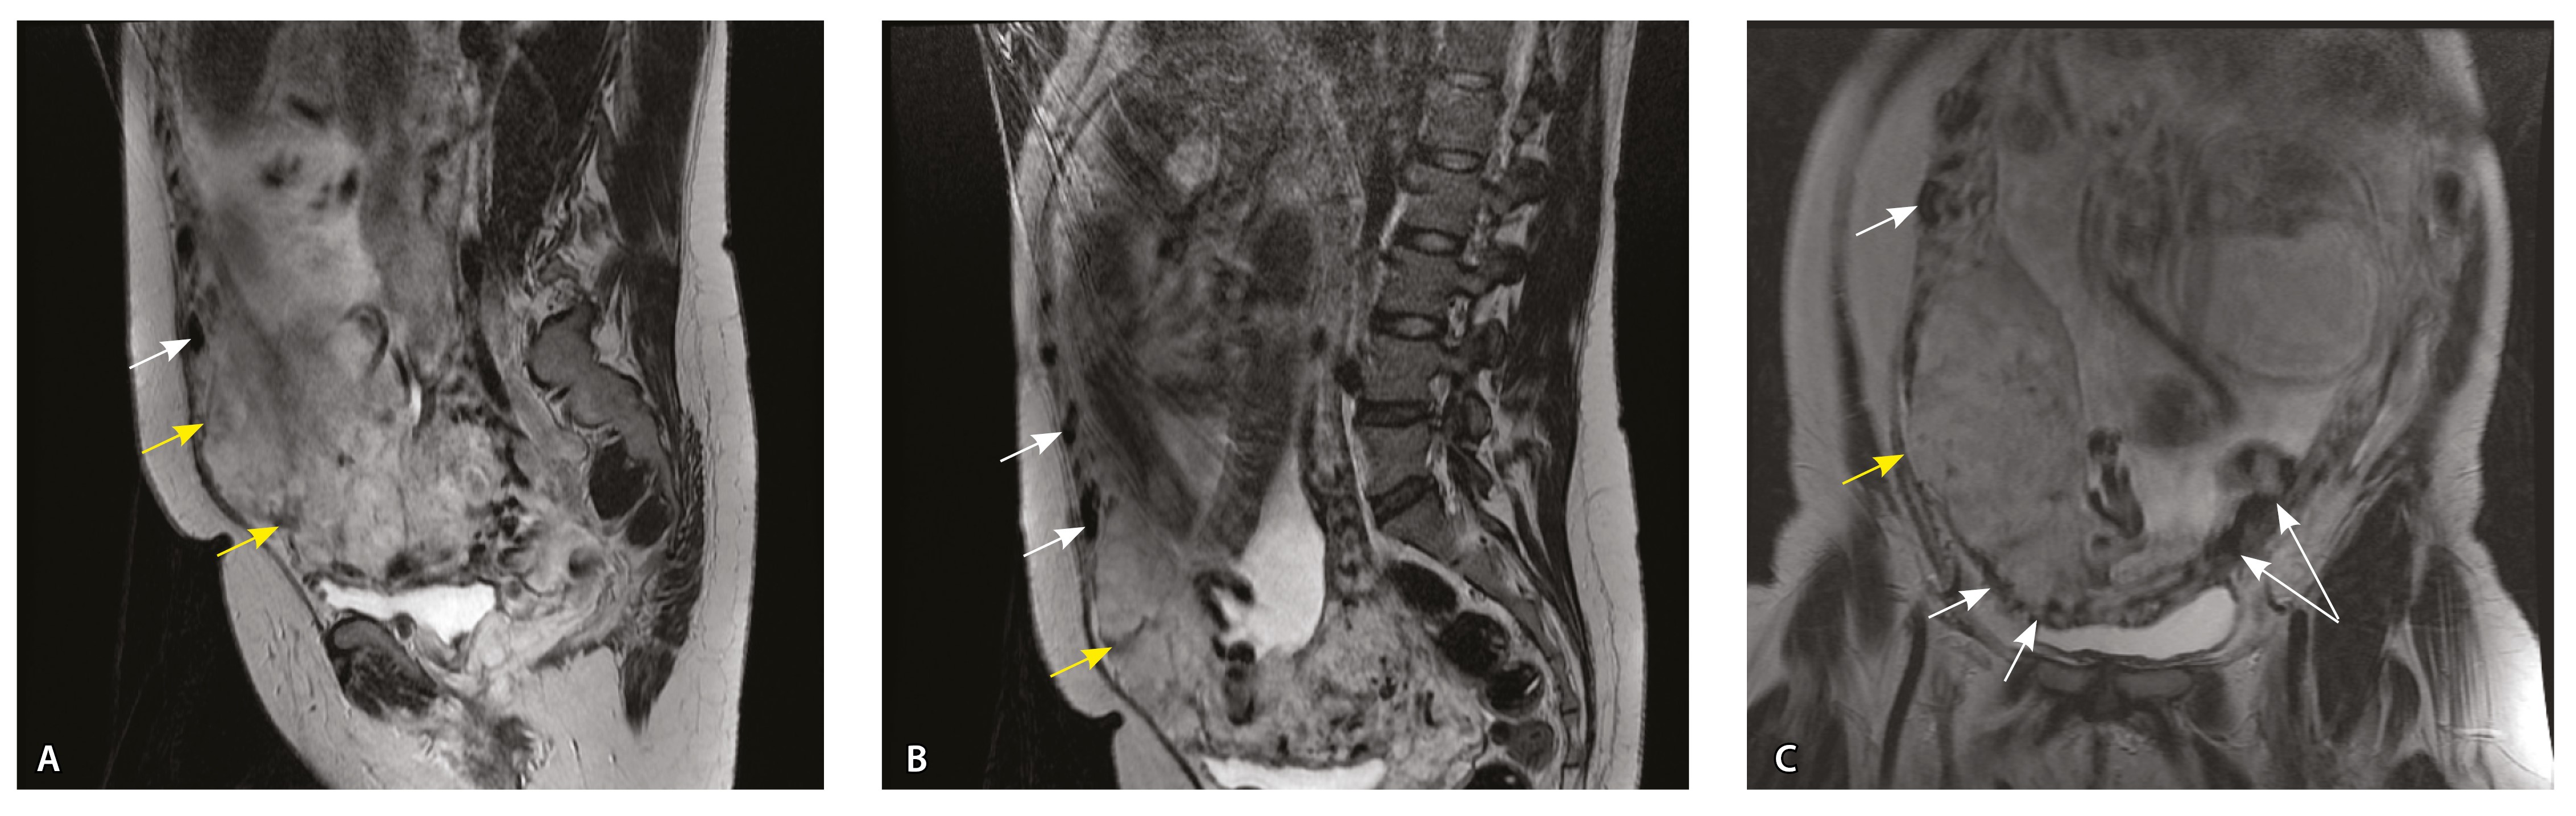

Сосуды 4-го типа. Наличие крупных извитых анастомозирующих сосудов, преимущественно по поверхности матки (в составе серозной оболочки матки) в сочетании с выраженным истончением нижнего сегмента матки (рис. 10).

Рис. 10. Беременность 33 недели, pl. percreta, PAS 3a по FIGO. На магнитно-резонансных томограммах в режиме Т2-взвешенного изображения в сагиттальной (A) и фронтальной (Б, В) плоскостях определяется внутриматочная гиперваскуляризация (желтые стрелки) и гиперваскуляризация в области выраженно истонченного нижнего маточного сегмента, с наличием многочисленных анастомозирующих сосудов по поверхности матки (белые стрелки); стенка матки в данной области представлена ретроплацентарными сосудами

Главным отличием крупных сосудов в составе серозной оболочки является то, что морфологически они находятся в пределах стенки матки. Об этом свидетельствует наличие в операционном материале тонкого поверхностного слоя мезотелия, отделяющего матку от брюшной полости (рис. 11). Его невозможно визуализировать методом МРТ из-за особенностей метода и толщины получаемых срезов.

Анализ частоты встречаемости сосудов 4-го типа при различных степенях приращения плаценты (рис. 14) показал: при плотном прикреплении плаценты (gr 2) и поверхностном приращении (gr 3) сосуды данного типа не выявлены, при pl. increta (gr 4) частота встречаемости незначительная – 16,7%, а при глубокой инвазии плаценты (pl. percreta, gr 5) сосуды этого типа преобладают (р < 0,001, хи-квадрат Пирсона).